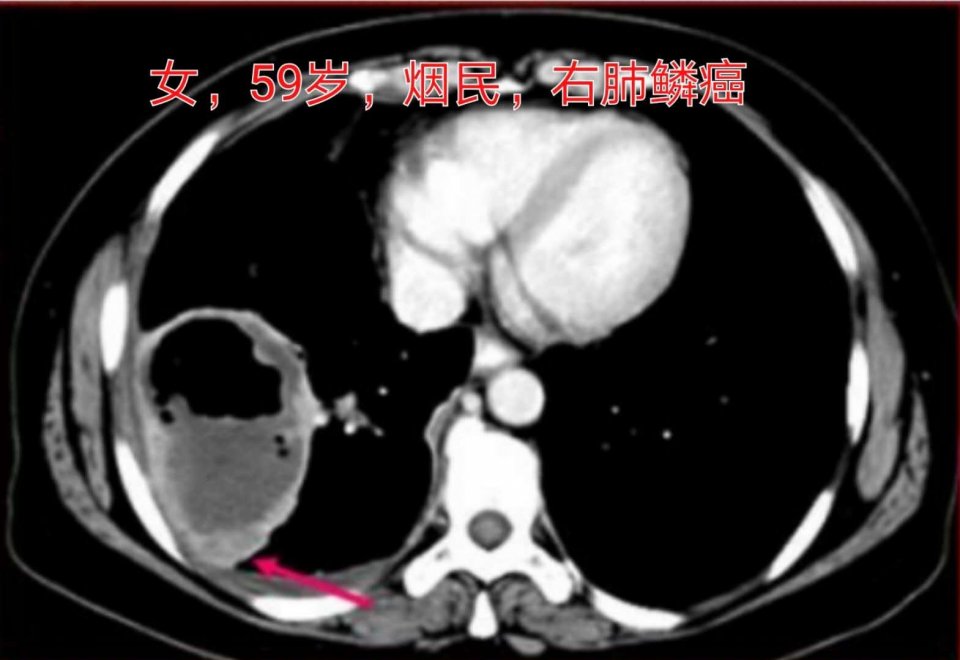

3.女性病人,59岁,老烟民,右侧肺鳞癌伴有巨大空洞形成:

这是一例周围型肺鳞癌,癌症肿块内发生了坏死,一部分坏死物经咳嗽排出,形成了大空洞。

肺鳞癌空洞有何意义?

Marcel (2014,EJR)的研究表明肺鳞癌空洞形成提示预后不良。

空洞型肺鳞癌中位生存期约17个月,而不伴有空洞形成的肺鳞癌,为92个月,差异悬殊!

肺癌有无空洞,是影响病人预后的独立因素。